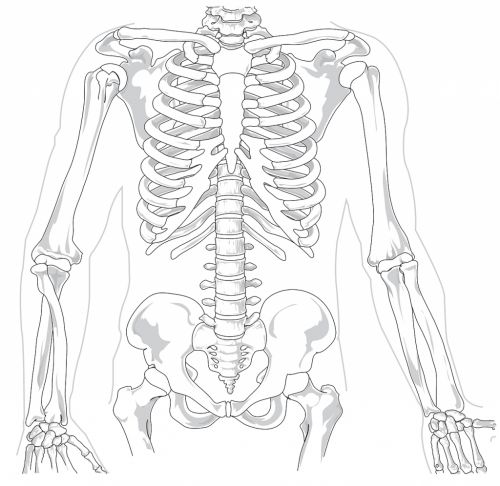

Позвоночник бежит от основания головы к копчику. Эта часть скелета дает структуру тела и поддерживает большую часть его веса, он также несет и защищает почти все основные нервные ветви, которые идут от мозга.

У позвоночника изящно изогнутая форма – она состоит из костей, известных как позвонки. У этих позвонков есть суставы между ними, чтобы позвоночник мог двигаться гибко. Кости позвонков разделены более мягкими, резиновыми тканями. Эти хрящевые поверхности и диски между позвонками дают плавное движение и подушку против любого воздействия на кости.